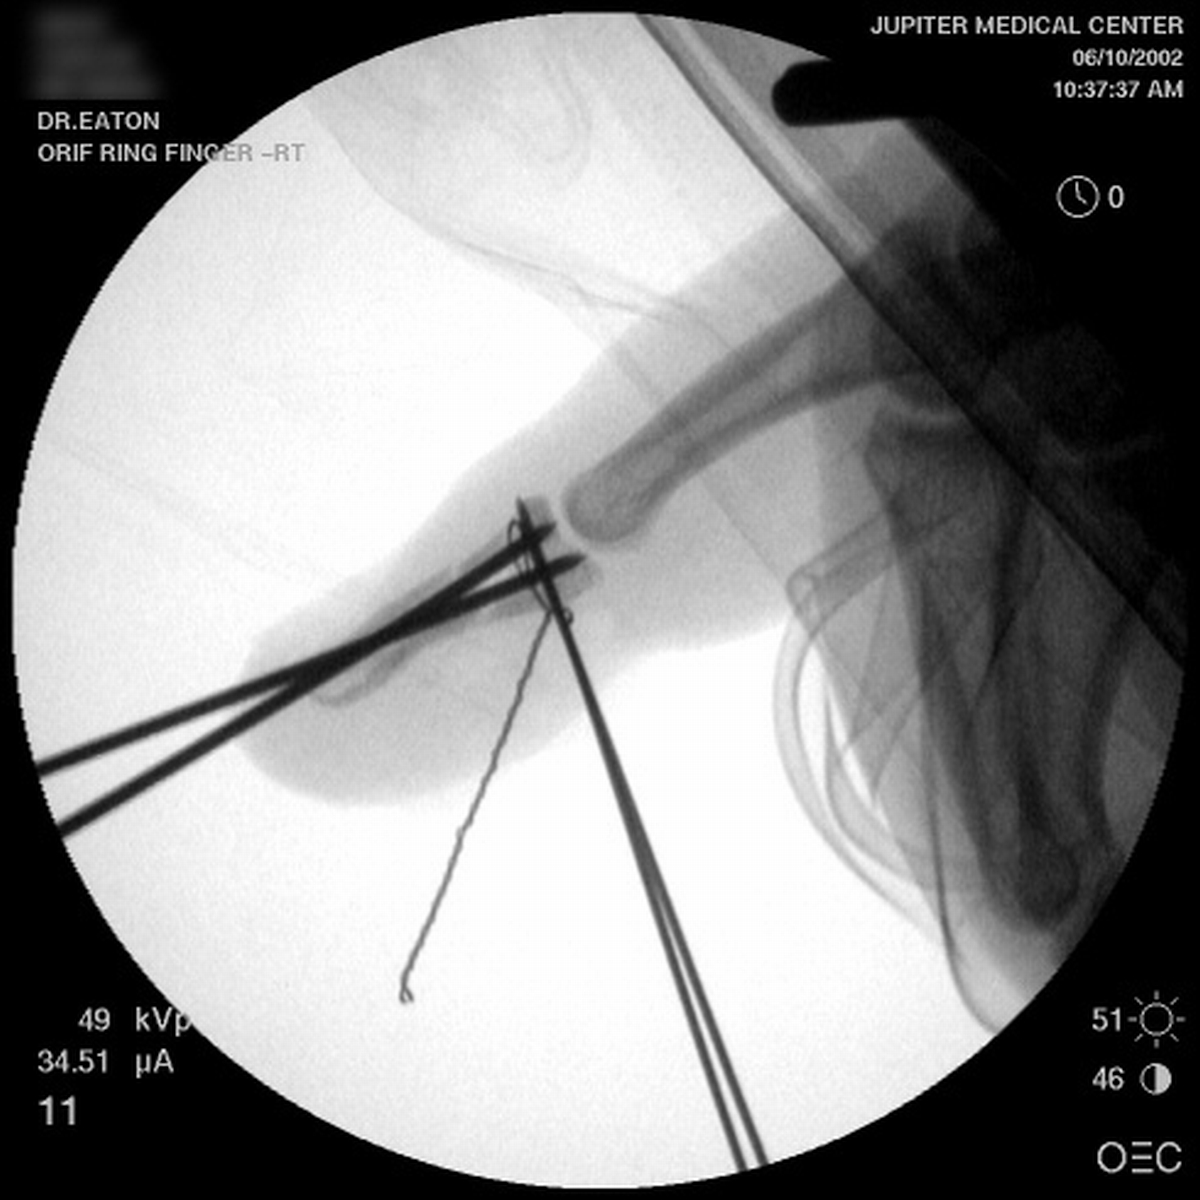

| A midline longitudinal palmar approach was used. This view shows a transverse pin across the dorsal proximal fragment, to be used as a path for interosseous wiring. Additional pins have been placed across each single cortex for later advancement. |